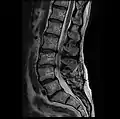

MRI lumbar spine with degeneration, post-hemilaminectomy L4-5 (sagittal T1 FSE)